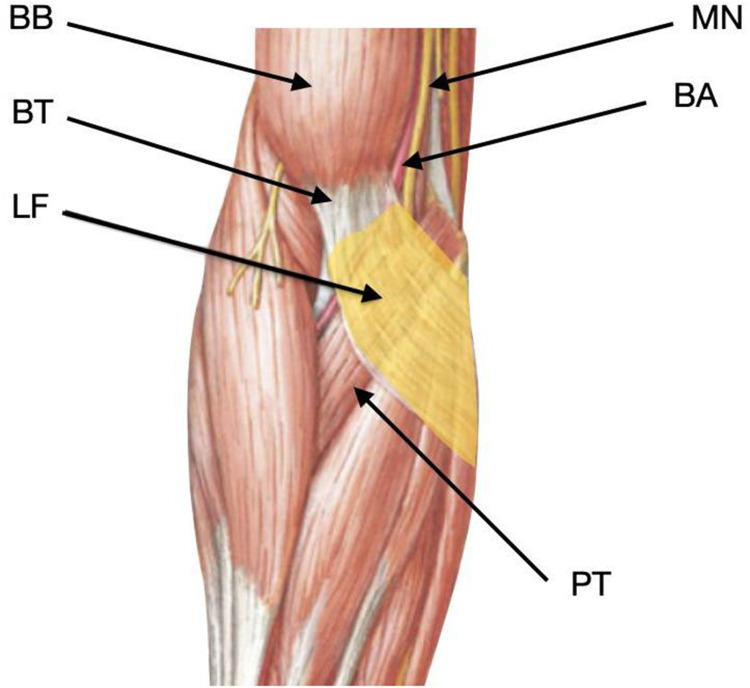

Background: The lacertus fibrosus serves as a site of entrapment for the proximal median nerve. Traditionally, surgical intervention has been the preferred method for resolution. This study demonstrates that perineural corticosteroid injection of the proximal median nerve entrapment under ultrasound guidance can improve nerve compression, strength, and pain in patients with lacertus fibrosus syndrome (LFS).

Methods: A retrospective quasi-experimental cohort study without a control group following the STROBE guidelines was conducted from July 2020 to May 2023. The patient selection was carried out considering Elisabet Hagert's diagnostic criteria. Ultrasound-guided proximal perineural corticosteroid injections were administered in the region of the lacertus fibrosus. Contingency tables were constructed to compare pre-and post-intervention data. The McNemar test was performed to evaluate the differences. Odds ratios (with 95% CI) were calculated to estimate the likelihood of improvement. A level of less than 0.05 was considered statistically significant. All analyses were performed using the R program.